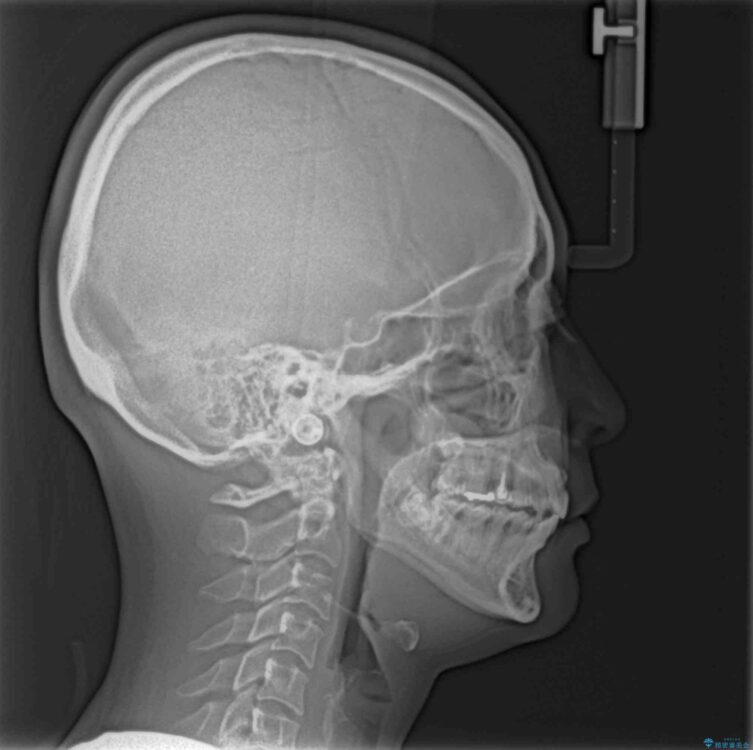

飛び出た上の前歯を気にして来院された患者様です。

奥歯の咬み合わせは、上顎歯列が理想的な一よりも数mm前方にある状態でした。

なるべく早めに治療を終えたいとのことで、補助装置を用いて上顎臼歯を後方に移動させ、同時にワイヤー装置にて整えることとしました。

舌の突出癖が原因で上下の歯に大きなスペースが生じていたため、舌のトレーニングをしっかり行っていただくことで、上顎歯列をスムーズに移動させることができました。